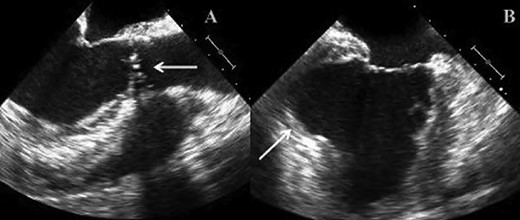

(A) TOE image showing bicuspid stenotic aortic valve. (B) TOE image demonstrating left ventricular apical aneurysm.

We report on a 57-year-old gentleman who initially presented with a 6-month history of heavy central chest pain, back and shoulder pain and shortness of breath on exertion (New York Heart Association Classification (NYHA) III, Canadian Cardiovascular Society Angina Classification (CCS) II). He suffered an inferior myocardial infarction in 2007 and has a known bicuspid aortic valve under follow-up. Risk factors for ischaemic heart disease include current smoking and a positive family history of heart disease on his maternal side. On admission, a transoesophageal ECHO (TOE) (Fig. 1) and cardiac magnetic resonance imaging (MRI) (Fig. 2) were carried out and demonstrated the bicuspid aortic valve with a mixed stenosis/regurgitation pattern (moderate–severe) (Fig. 1A). In addition, marked left ventricular dilatation and an inferior LVA extending from the base to the mid-cavity of the left ventricle measuring 4.5 cm across the orifice (Fig. 1B) were seen. The aneurysm was thin walled, with dyskinetic motion with evidence of a dense thrombus adherent to the wall. The inferior wall was noted to be akinetic and non-viable. Preoperative LVEF was 60%. The angiogram showed stenosis of the right coronary artery (Fig. 3B) in the mid-segment together with distal left anterior descending disease (Fig. 3A).